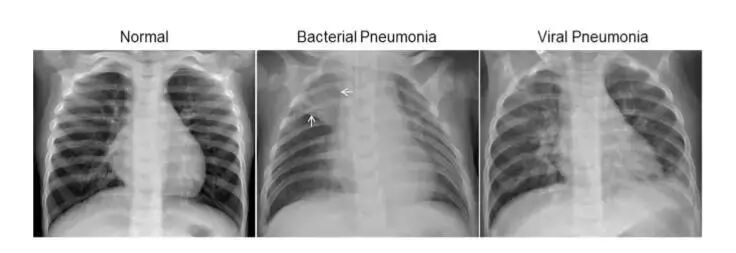

• 临床突破:2018年2月23日,华人学者张康教授团队带来的AI影像诊断系统荣登《Cell》封面,该系统能精确诊断黄斑变性和糖尿病性黄斑水肿这两种眼病,还准确地区分细菌性和病毒性肺炎。

• 试验研究:诊断黄斑变性、黄斑水肿的准确性达到96.6%,灵敏性达到97.8%,特异性达到97.4%,检测准确率达到曲线下面积99.9%。区分细菌性肺炎和病毒性肺炎的准确性达到90.7%,灵敏性达到88.6%,特异性达到90.9%。

• 针对疾病:年龄相关性黄斑变性和糖尿病性黄斑水肿,儿童细菌性和病毒性肺炎